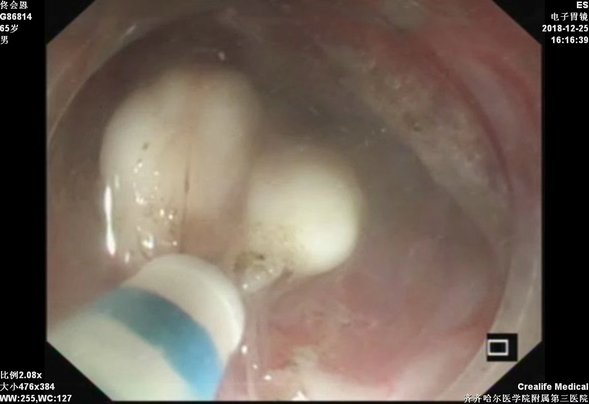

贲门黏膜下肿物

隧道内剥离病灶